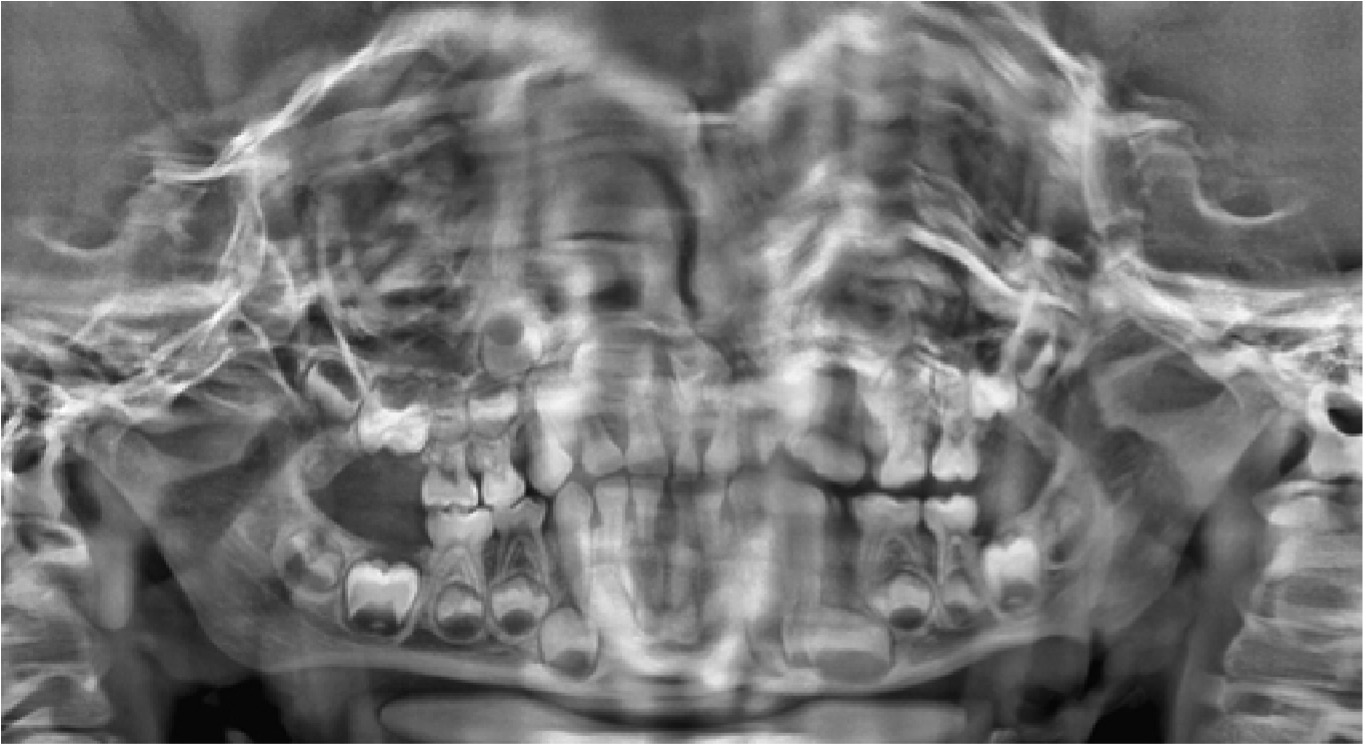

En 2015, cuando el paciente tenía 3 años y 8 meses, la madre fue en busca de explicaciones para dichas alteraciones. En la anamnesis fue relatado que los primeros dientes primarios erupcionaron alrededor de los 12 meses de edad y que la madre notó alteración del color desde el inicio, pero como la pediatra la había alertado sobre la alteración de color, no buscó rápida atención. Durante el examen clínico se observó coloración verde en todos los dientes prmarios presentes; la pigmentación se localizaba en los incisivos centrales y laterales superiores e inferiores en toda extensión de la corona hasta el tercio cervical. En los caninos inferiores la coloración verde se extendió desde el borde incisal al tercio medio de la corona. Los primeros y segundos molares inferiores y superiores estaban afectados en casi toda la extensión de la corona por un tono verde oscuro, y apenas el tercio cervical no presentaba coloración (Figuras 1 y 2). Los dientes primarios presentaron una morfología normal (esmaltes con superficies lisas y regulares), buenas condiciones de higiene bucal (bajo índice de placa dental) y ausencia de manchas blancas, lesiones de caries y de hipoplasias y movilidades. Los tejidos blandos estaban íntegros y presentaban coloración normal. En las radiografías no se observó ninguna alteración (Figura 3).

Figura 3: Radiografía panorámica. Paciente con edad de 3 años y 8 meses.